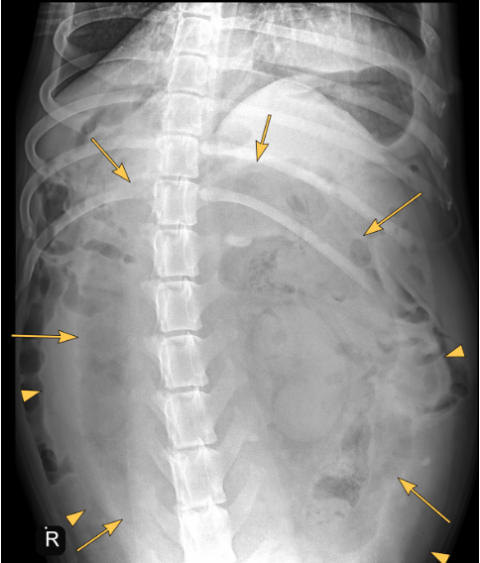

There is severe distention of the abdomen. As far as included the extra-abdominal soft tissues are within normal limits. There are 8 lumbar vertebrae, otherwise the bony structures are within normal limits.

A large well-defined, rounded soft tissue mass is noted in the caudal mid and cranial abdomen. The mass is filled with combination of fluid ( yellow arrow points) and gas (yellow arrows) and originating from the uterus.

The mass is displacing the gastrointestinal tract dorsally, cranially and laterally.

Large fluid and gas-filled mass in the caudal, mid and cranial abdomen originating from the uterus (emphysematous pyometra). Considering the shape of the mass a torsion is suspected.